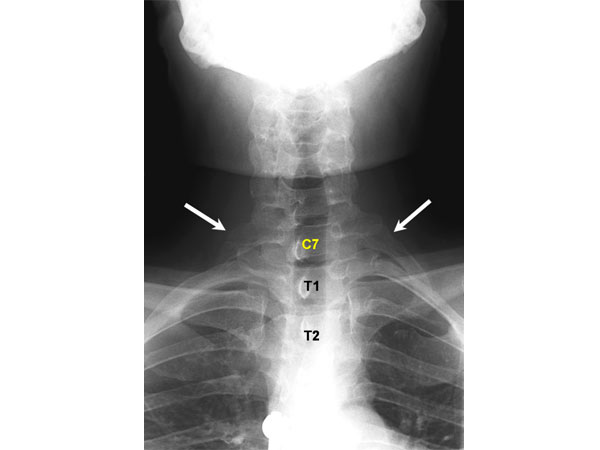

పక్కటెముకలు ఎక్కువగా ఉండడం

సాధారణంగా అందరికీ పక్కటెముకలుంటాయి. కానీ కొందరికీ మాత్రం అదనంగా ఉంటాయి. అలా ఉండడం ప్రమాదకరం కాదు. అమ్మాయిల్లో ఎక్కువగా ఇలా అదనపు పక్కటెముకలుంటాయి. వీటిని సర్వికల్ రిబ్స్ అంటారు. ఇలా అదనపు ఎముకలుండేవారు కూడా చాలా అరుదుగా ఉంటారు.